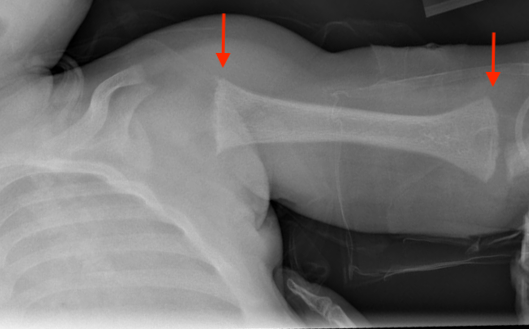

A radiologic skeletal survey demonstrated abnormal bone mineralization, fraying, splaying, and cupping of numerous sites bilaterally (femora, tibiae, fibulae, radii, ulnae). There was also mild expansion of the anterior rib ends at the costochondral junction bilaterally (Figures 1-4).

Figure 1. Radiologic skeletal survey demonstrated abnormal bone mineralization (arrows).

Figure 2. Radiologic skeletal survey demonstrated fraying, splaying, and cupping of the humeri at the proximal and distal ends bilaterally (arrows). There was also mild expansion of the anterior rib ends at the costochondral junction bilaterally.